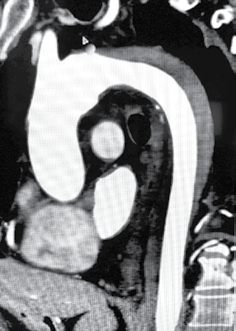

Durante a investigação na emergência, realizou a tomografia de tórax apresentada a seguir.